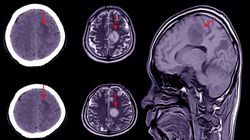

Witam. Chciałabym się spytać o interpretację wyniku usg przezciemiaczkowego. Oto opis : Układ komorowy nieposzerzony symetryczny, nieprzemieszczony. Struktury muzgowia o typowej echogeniczności. Przestrzeń podoponowa na sklepistosci mózgu poszerzona do 7mm. CSP o szerokości 10mm. Natomiast w pierwszym usg CSP o szerokości 7mm. Reszta w porzadku.